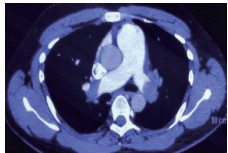

例4 62岁,女性,主诉“活动后气短20 d,加重1 d伴晕厥1次”。患者入院20 d前上近20级台阶后感气促,休息后缓解,未重视。入院前1 d,突发晕厥伴有轻微活动后明显的呼吸困难。既往:左下肢静脉曲张病史3~4年;入院40 d前患者左足跖骨骨折,接受外固定,尚未影响日常活动,未接受抗凝治疗;发现血小板减少数年(血小板维持5.5~8.6 g/L,末次于一年前血小板85 G/L),未明确原因及治疗;血气分析提示pH 7.447,PaCO2 32.2 mmHg,PaO2 85.3 mmHg,SaO2 96.8%;D-Dimer 1 947 ng/mL;FDP 22.84 μg/mL,FBG 2.05 g/L;PLT 51G/L;cTnI 0.52 ng/mL,BNP 299 pg/mL;ALT 318 U/L,AST 300 U/L,CREA 74.8 μmol/L,血Na+、K+、Cl-:正常范围;UCG提示:右心大,肺动脉主干轻度增宽(28 mm),三尖瓣反流(重度),反流面积13.7 cm2,TI法估计SPAP为30 mmHg、左室舒末内径35 mm、左室舒张功能受限(E/A 1:1.5)、未见节段性室壁运动障碍;双下肢静脉超声提示左侧腘静脉不完全血栓。心电图(图 12所示)提示窦性心动过速、SⅠQⅢTⅢ;CTPA显示肺动脉分叉处及双肺亚段充盈缺损(图 13所示)。

| 图 13 入院时CTPA结果显示肺动脉分叉处及双肺亚段充盈缺损 |

入院查体:神志清楚,体温36.5℃,血压120/70 mmHg,脉率110次/min,呼吸22~26次/min,指氧饱和度93%(安静,空气氧),未见乏氧征。双肺呼吸音清,未闻及干湿性啰音,心率110次/min,律齐,P2 > A2,心界无扩大,无杂音,腹软,无压痛,肠鸣音正常。神经系统未见异常。左下肢膝关节以下可见静脉曲张,双下肢无浮肿。入院诊断:急性肺血栓栓塞症(中高危);左下肢静脉曲张并血栓形成;血小板减少症;肝功能不全。处理方法及原因:患者中年,日常生活质量高;入院20 d前虽有症状,但入院1 d前明显加重并出现晕厥发作;两次D-Dimer检查均<2 000 ng/mL,与CTPA显示的血栓负荷不匹配。入院后连续两次检测血小板均低于正常(51~77 g/L)。因考虑病史较长但近期有加重、血小板低等原因系统溶栓治疗出血风险较大,所以给予导管介入碎栓并行肺动脉内溶栓治疗(r-tPA 20 mg)。溶栓2 h后患者症状明显缓解,复查D-Dimer 12 560 ng/mL,序贯肝素抗凝并复查CTPA提示原有血栓明显消失(图 14所示)。

| 图 14 介入溶栓后患者CTPA结果提示明显改善 |

患者特点及再灌注治疗时机及方式选择:患者病程20 d,但是入院前1 d呼吸困难加重同时伴有晕厥,提示1 d内有明确的新的血栓脱落导致的一过性脑缺血。理论上讲,如果纤溶功能正常的话,CTPA显示的血栓负荷与D-Dimer具有一定的匹配性,而本例患者连续两次检测并未发现这种匹配的特点,分析原因有两种可能:①原有主肺动脉干血栓负荷较大,近期虽然有新的血栓脱落,但新鲜血栓的负荷量不足以大到D-Dimer明显升高的地步;②主干血栓为近期一次脱落而成,但是患者有存在继发纤溶低下的可能,同样表现为较低的D-Dimer水平。如果存在继发纤溶功能低下的话,难以避免单纯抗凝治疗后栓塞性肺动脉高压的风险。我们决定给予介入下的碎栓并肺动脉内溶栓治疗是考虑原有血栓阻塞左右肺动脉主干,很难代偿新鲜血栓的再次脱落。更重要的是,CTPA提示肺动脉主干的骑跨血栓密度尚不支持陈旧血栓。溶栓后CTPA结果也验证了对CTPA结果解读的正确。本例患者另一个特点D-Dimer水平与血栓负荷不成比例的另一个依据是凝血机制检测提示纤溶系统异常,PAI-1活性超过正常3倍,证实了最初的判断。